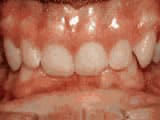

Crowding of the teeth

Before

AfterThis boy started treatment at age 11 and wore braces for 26 months. He loves his new smile.